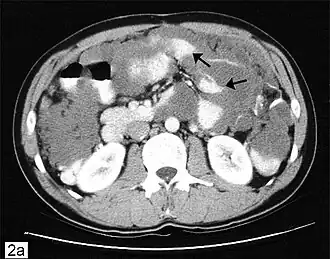

| Tomografia computadorizada de múltiplos pseudomixoma peritoneal (setas). | |